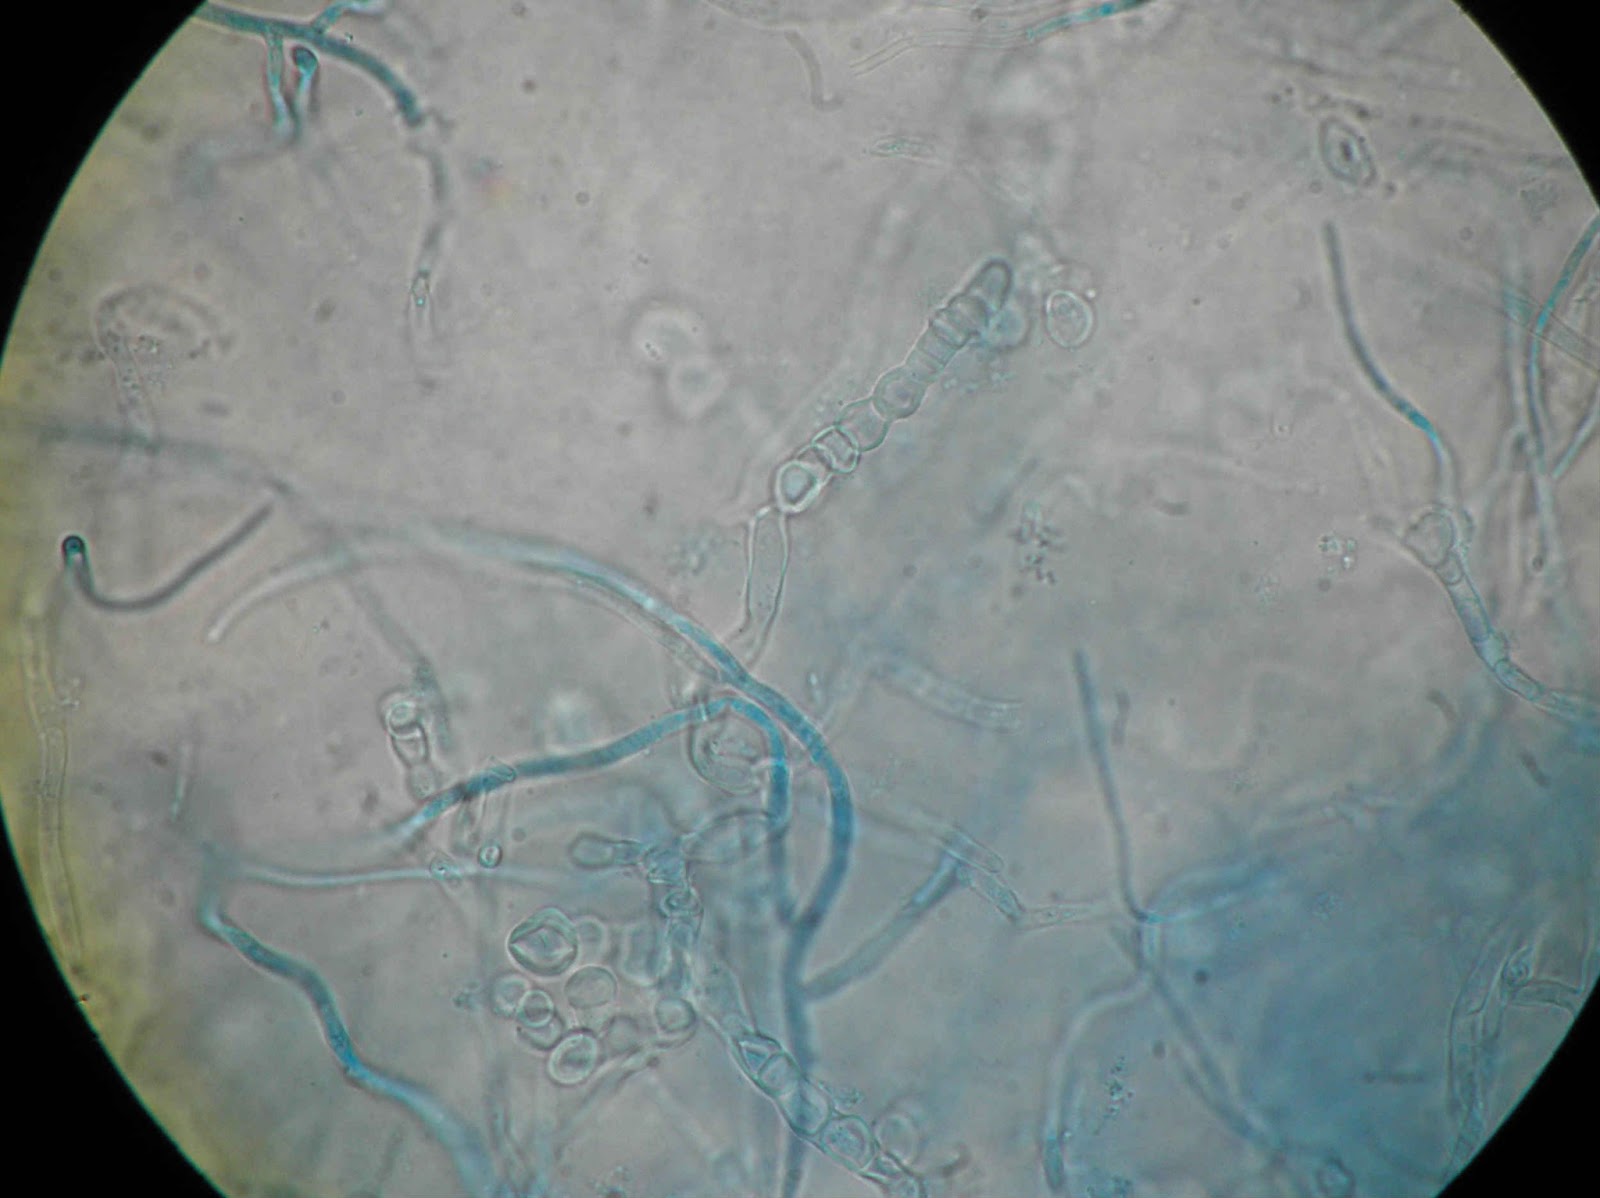

Ao exame microscópico observam hifas septadas de modo a apresentar artroconidios cilindricos ou elipsoides

| Repicagem com 30 dias de incubação. |